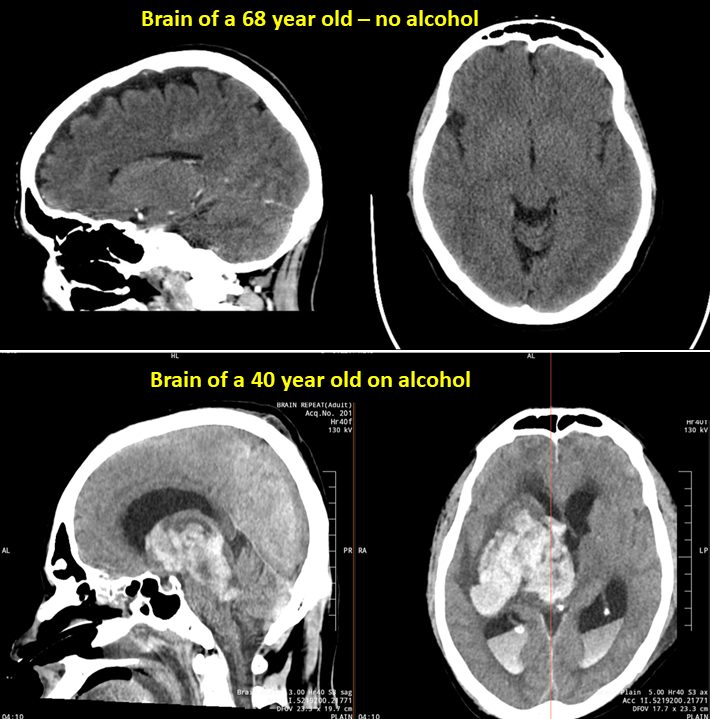

A patient decided to party last weekend and is now battling for life on the ventilator. He won't make it. See what alcohol does to the brain. It is not just the liver you need to worry about. Alcohol is a systemic poison. It damages everything in its path. The big white blotches